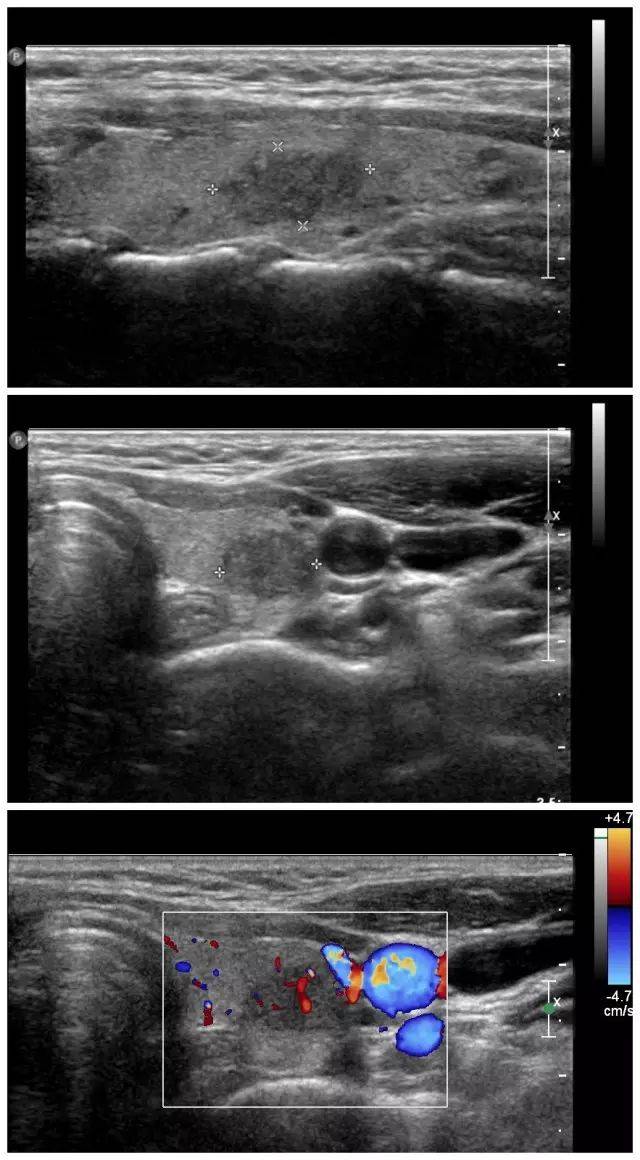

超声诊断甲状腺乳头状癌累及包膜1例原创

图片尺寸1080x1440